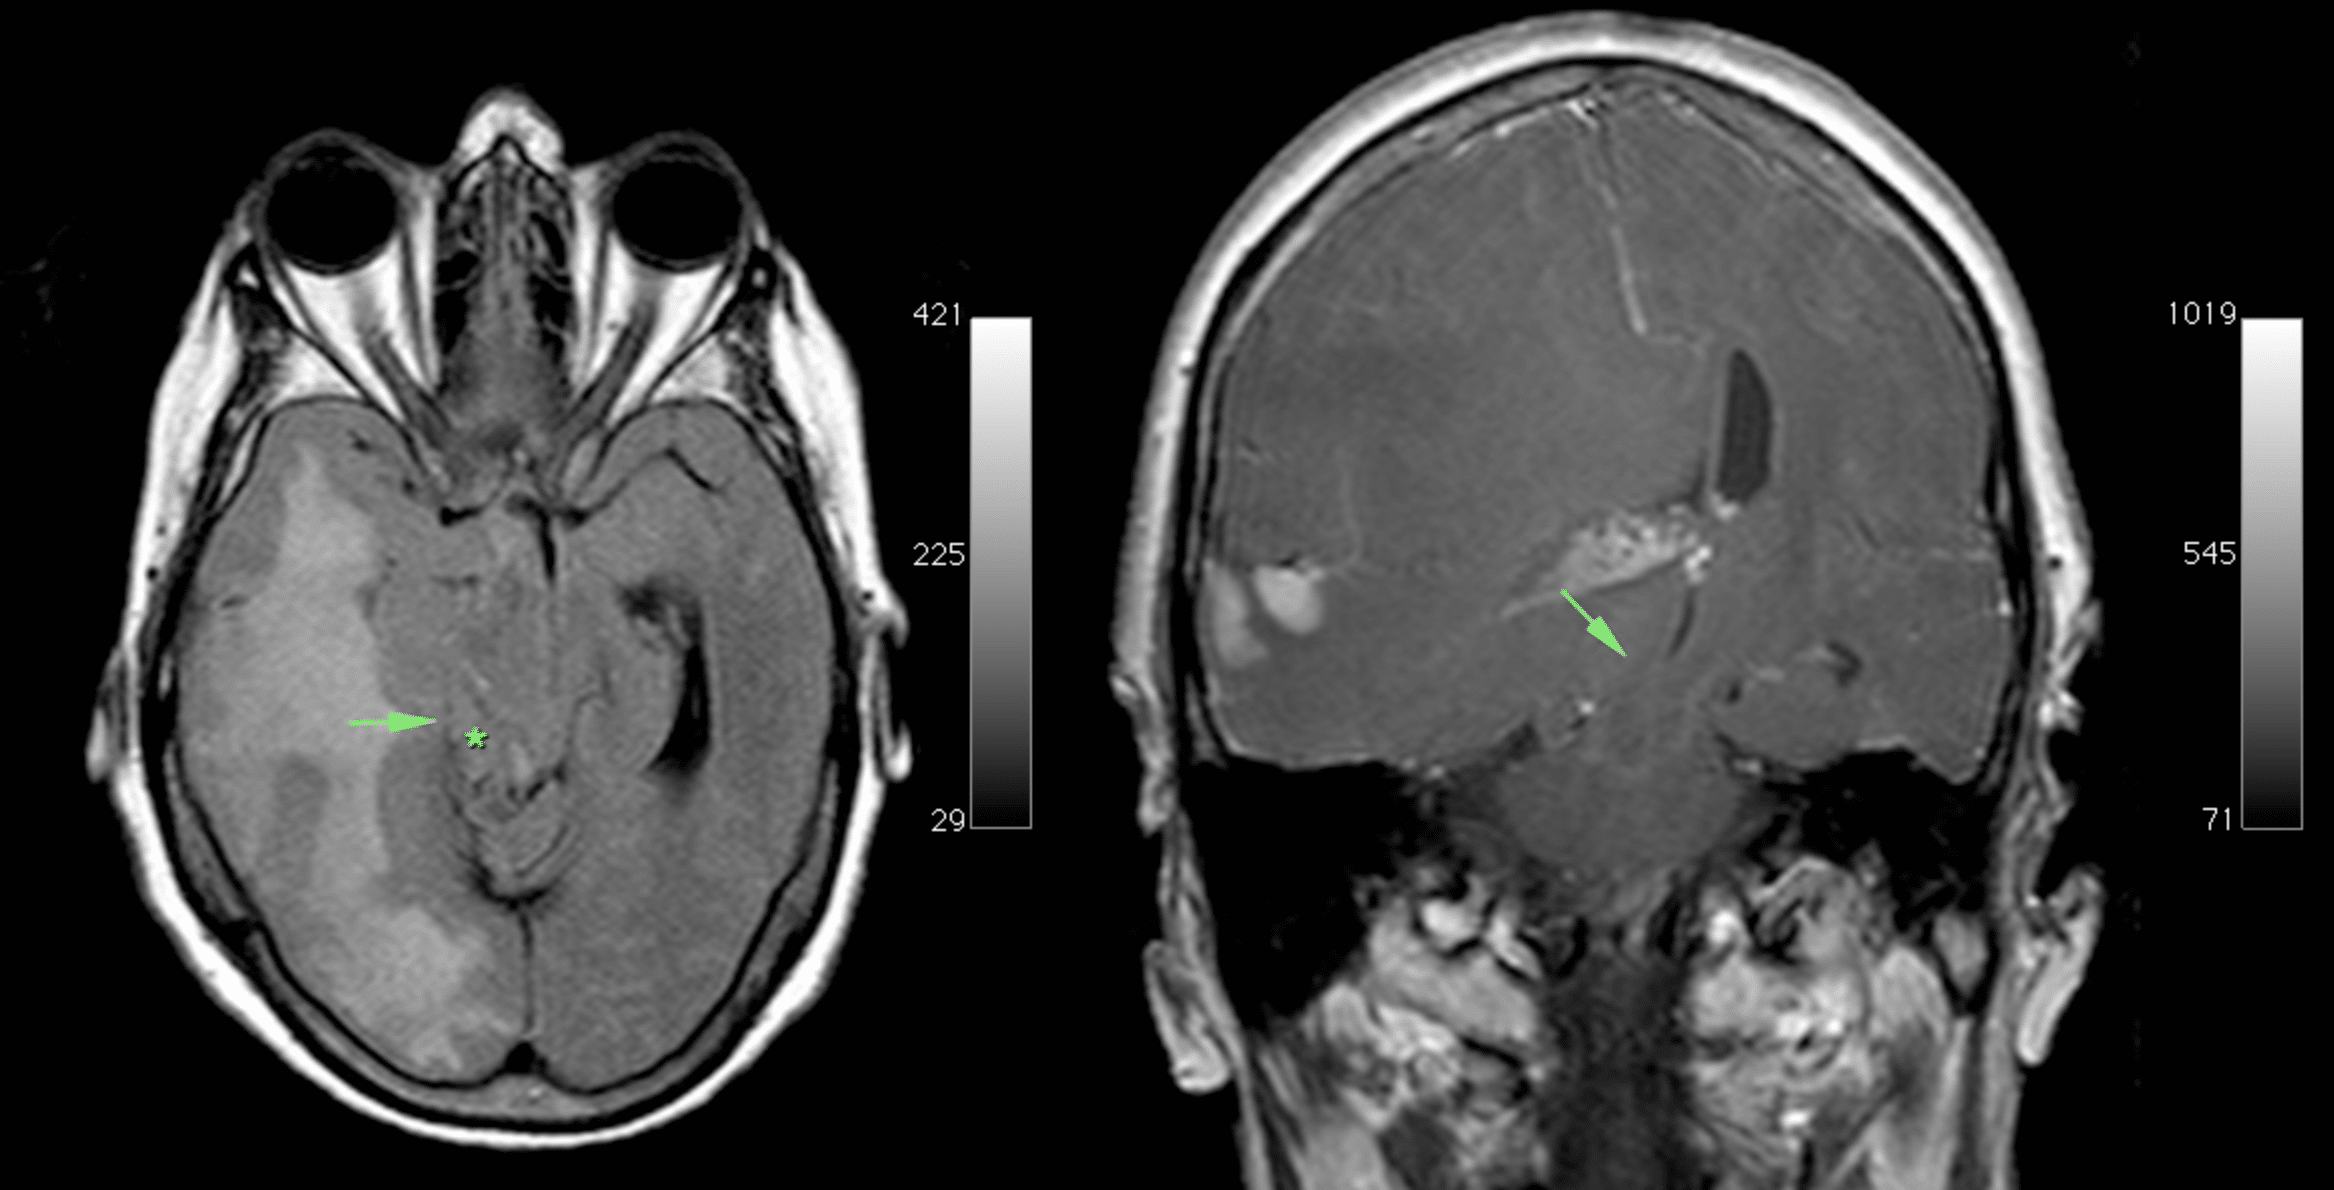

Mass effect of the tumour, with medial part (uncus) of the right temporal lobe (arrow) is herniating over the edge of the tentorium (*) compressing the mesencephalon against the free edge of the contralateral tentorium and causing a notch on the left side. Case courtesy of Erik Ranschaert, Radiopaedia.org, rID: 10967